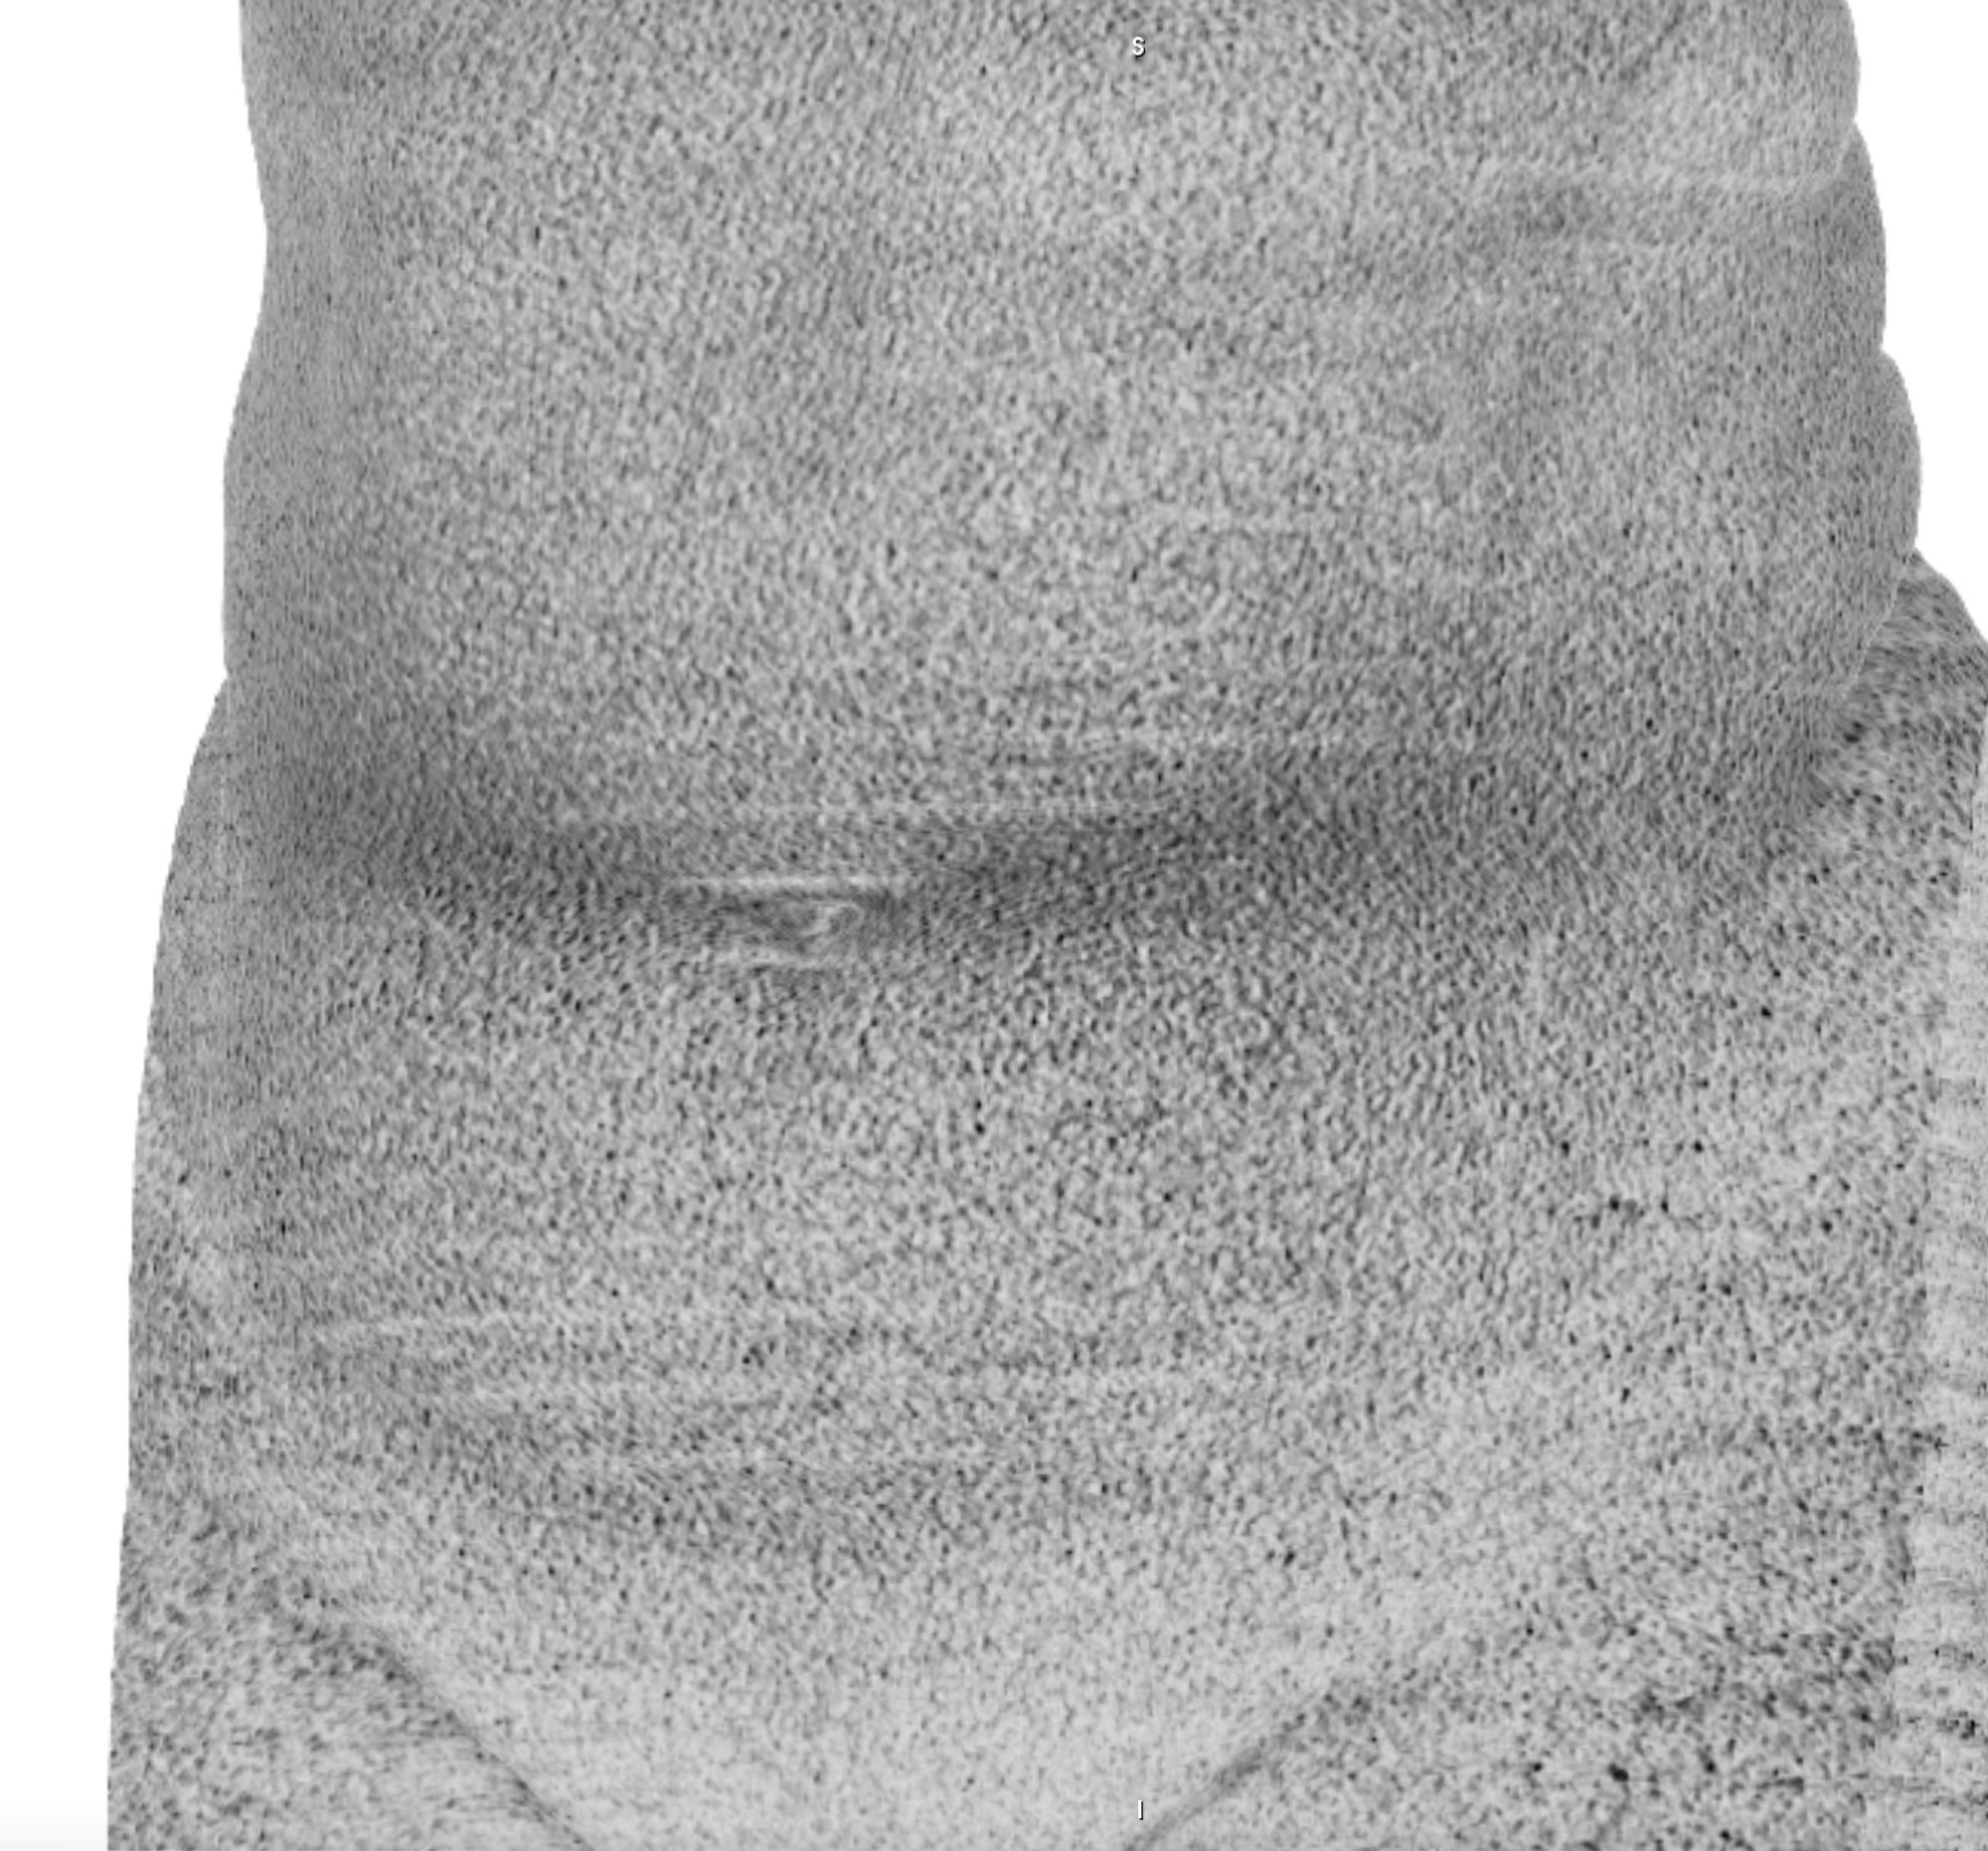

The history of medicine can be understood as an on-going endeavour to comprehensively visibilise the body, to pull it from obscurity, to open it out to vision. ‘The x-ray image, with its simultaneous view of the inside and outside, turned the vantage point of the spectator-subject inside out.’ * With the invention of the x-ray, the surface of the body, and its distinction from the world, was dissolved and lost in the image.

In this project, I look at the visual limit between the inside and the outside, the inner and the outer. I combine different visual approaches to materialise the body, using medical imagery, photography from manuals and radiology software. Decontextualised from their origin, these images speak of medicine’s relationship to both sex and violence, and remind us that, in medicine, to go into the body is always to go into the image first.